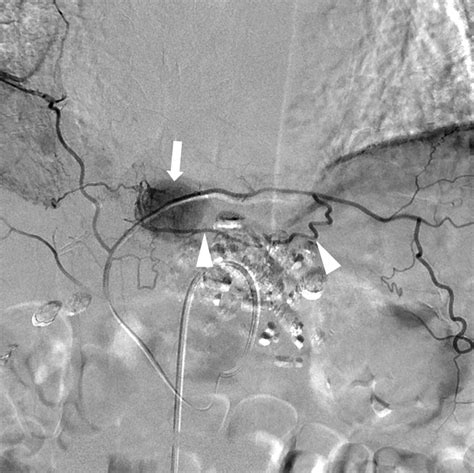

In the modern medical landscape, the Inferior Phrenic Artery has gained immense importance, particularly regarding Hepatocellular Carcinoma (HCC). When treating liver tumors that are supplied by the hepatic artery, interventional radiologists often encounter situations where the tumor has recruited extrahepatic collateral blood supply.

The right IPA is the most common collateral source for these tumors when the hepatic artery supply is compromised or insufficient. During Transarterial Chemoembolization (TACE), identifying and catheterizing the IPA is often necessary to ensure that the tumor receives the full intended dose of therapeutic agents.